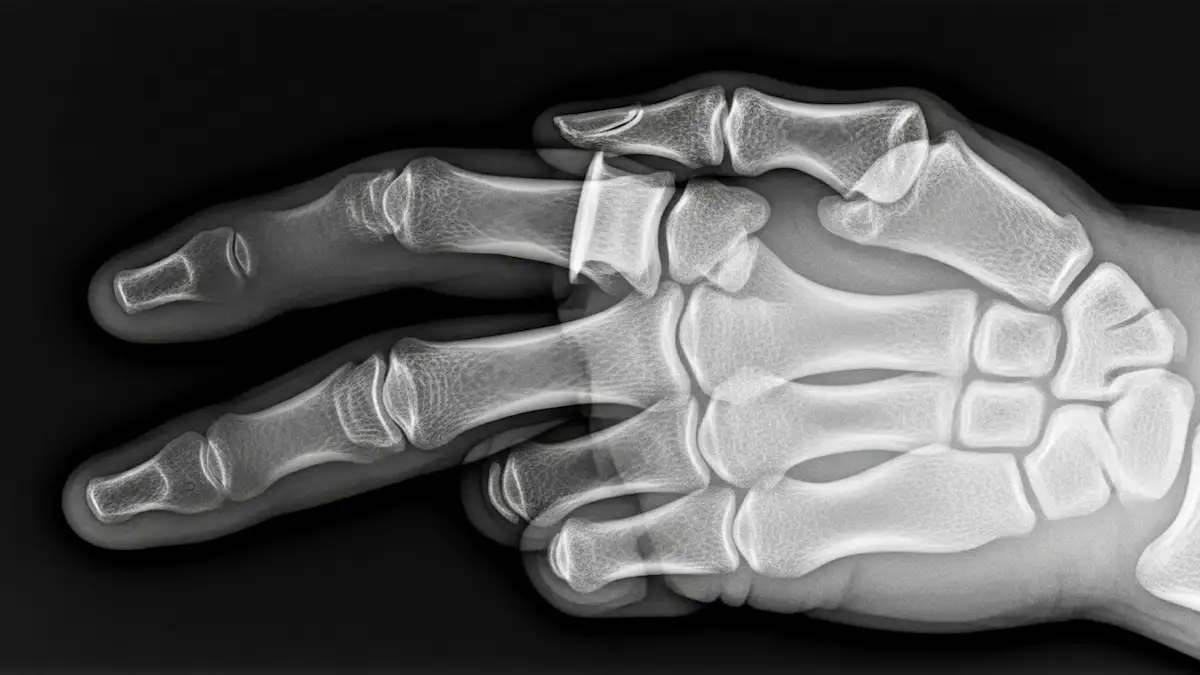

Radiografias em diferentes ângulos são solicitadas para confirmar a luxação e descartar fraturas associadas.

A luxação do dedo é o deslocamento dos ossos da articulação, com perda do alinhamento anatômico normal.

Na maior parte dos casos, o problema envolve as articulações interfalângicas, principalmente a interfalângica proximal, localizada na porção média do dedo.